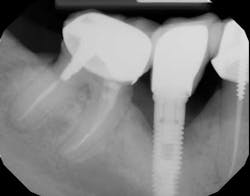

A 52-year-old woman with a noncontributory medical history, taking no medications with no reported food or drug allergies, was referred to my office from a general dentist in order to obtain a second opinion. She had a lower right premolar implant placed in an oral surgery office five years ago that was suffering from severe peri-implantitis. (Fig. 1) Her first dentist told her that the implant had to be removed and that her treatment options were a fixed partial denture in the form of a three-unit bridge or a partial denture because re-implantation was not feasible. In addition, he sent her to a periodontal office that verified his statement, telling the patient that because of nerve proximity and the poor chance of ridge augmentation, re-implantation was unlikely. When she asked if saving the implant was possible, both the dentist and the periodontist told the patient that because of the level of bone loss, regenerative treatment would not work.Fig. 4